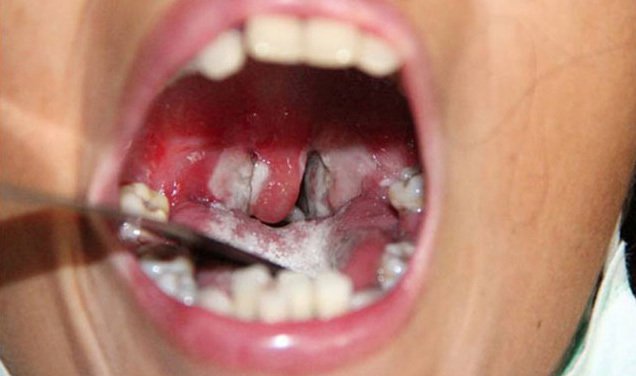

- Bạch hầu họng

Gặp chủ yếu có tới hai phần ba trường hợp là amidan. Các triệu chứng thường gặp nhất là đau họng, khó chịu, nổi hạch cổ dưới hàm và sốt nhẹ. Phát hiện sớm nhất ở hầu họng là ban đỏ nhẹ, có thể tiến triển thành các đốm rải rác của dịch tiết màu xám và trắng. Trong ít nhất một phần ba trường hợp, có màng giả mạc tại nơi họng viêm gây ra sự hình thành một pseudomembrane kết hợp (bao gồm fibrin hoại tử, bạch cầu, hồng cầu, tế bào biểu mô và vi khuẩn) (hình 1). Màng này bám chặt vào các mô bên dưới và chảy máu khi cạo.

Trẻ mệt nhọc da xanh do độc tính toàn thân tăng lên khi pseudomembrane lây lan từ vùng amidan ra xung quanh.